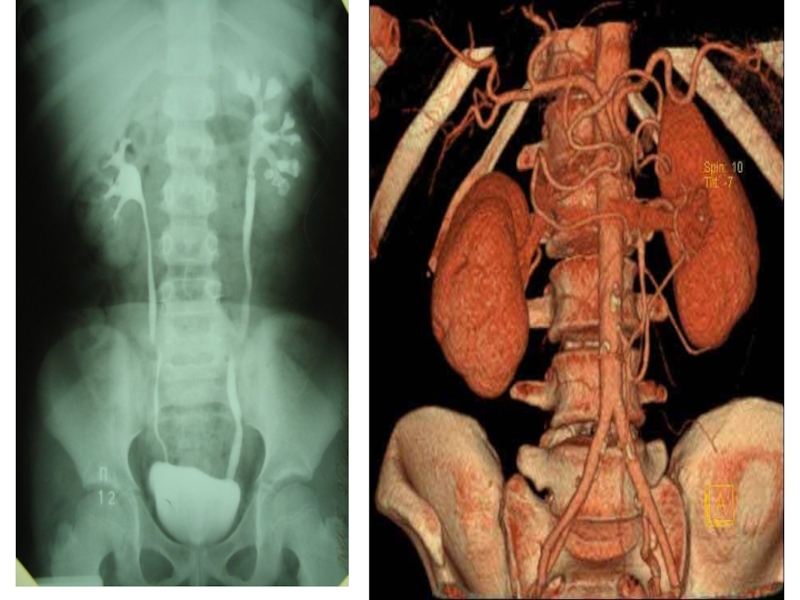

Слайд 91Экскреторная урография:справа- камень левого мочеточника, слева – симптом “белой почки “

Слайд 93Экскреторная урография:справа обтурирующий камень мочеточника, слева- 2-сторонние камни

Слайд 94Экскреторная урография:обтурирующие камни правого мочеточника

Слайд 95 Экскреторная урография:справа- дефект в

лоханке слева, слева-дефект в ПУС